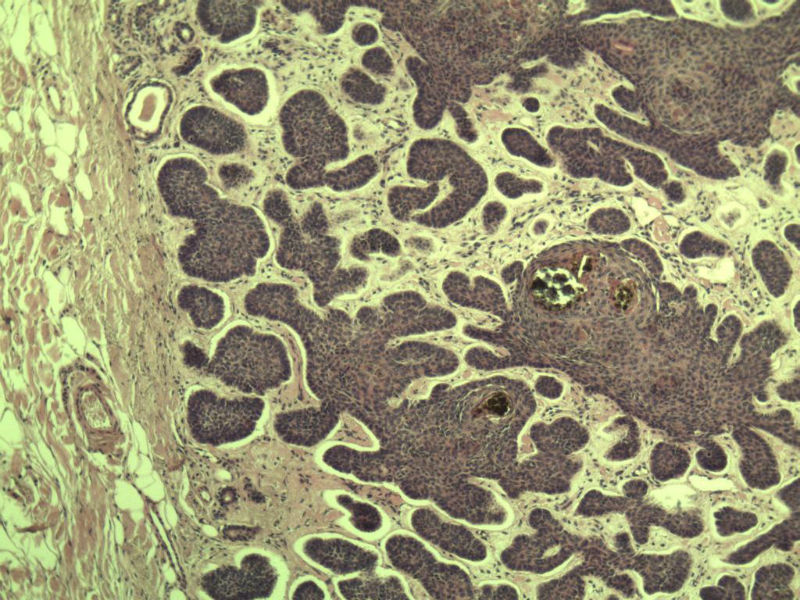

女 67岁 临床考虑面部色素痣 1*0.8 cm  请问各位老师 这是什么? 谢谢!面部包块图1

毛母/发细胞瘤鉴别基底细胞癌,可做CD10,CK7,CK20鉴别

考虑毛发上皮瘤,需除外基底细胞癌。

毛发上皮瘤,需与基底细胞癌鉴别

第一例:毛发上皮瘤

第一例:毛发上皮瘤,与基底细胞瘤区别明显。

第一例  毛发上皮瘤,和基底细胞癌鉴别一下

第一例考虑毛母细胞瘤,第二例考虑基底细胞癌。

毛母细胞瘤

第一例:毛母细胞瘤;第二例:基底细胞癌

第一例,毛发上皮瘤;第二例,基底细胞癌。

一毛发上皮瘤